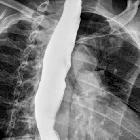

Plain radiograph

Chest radiograph findings include:

- convex opacity overlapping the right mediastinum. Occasionally may present as a left convex opacity if the thoracic aorta is tortuous.

- air-fluid level due to stasis in a thoracic esophagus filled with retained secretions and food

- small or absent gastric bubble

- anterior displacement and bowing of the trachea on the lateral view

- patchy alveolar opacities, usually bilateral, may be seen. These represent acute pneumonitis or chronic aspiration pneumonia related to dysphagia.